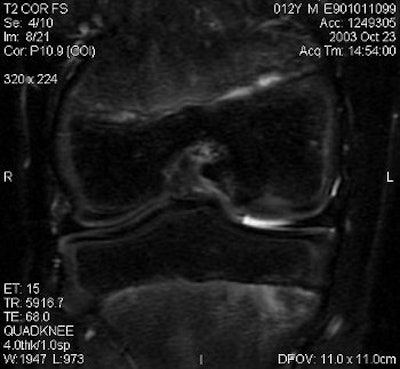

|  |

| Above and below, OCD of the medial femoral condyle in a female child. Images courtesy of Dr. Douglas Beall. |